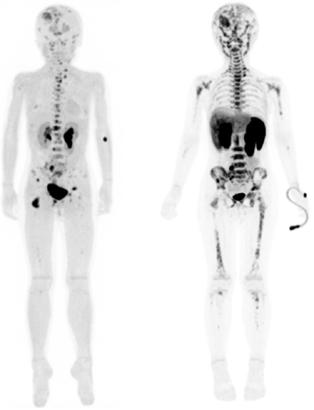

Figura 1A) Estudio PET con 6-[18F]FDOPA positivo para actividad tumoral del primario conocido en abdomen y retroperitoneo, con metástasis difusas en la médula ósea del esqueleto axial y apendicular.

Figura 1B) Estudio PET con [18F]OCTREOTIDE con sobreexpresión anormal de los receptores de somatostatina en retroperitoneo y esqueleto axial y apendicular.

Al correlacionar con 6-[18F]DOPA (Figura 1A) se observa que las lesiones tienen mayor sobreexpresión de los receptores de somatostatina.

Femenino de 7 años con diagnóstico de Neuroblastoma, se realiza PET/RM con [18F]F-DOPA para estadiaje, con evidencia de lesión primaria a nivel de retroperitoneo y conglomerados locoregionales así como infiltración a médula ósea del esqueleto axial y apendicular (Figura 1A), posteriormente la paciente fue tratada quirúrgicamente con resección de la lesión primaria así como tratamiento con inmunoterapia y transplante autólogo de médula ósea además de radioterapia. Al presentar refractariedad al tratamiento comentado, se plantea la posibilidad de administrar Lutecio (177Lu) oxodotreotide, por lo que se sugiere realizar PET/RM con [18F]Octreotide para valorar expresión de receptores de somatostatina y considerar la terapia con radionúclidos para receptores de péptidos (PRRT), el estudio muestra evidencia de sobreexpresión anormal de dichos receptores en retroperitoneo, espacio subpleural izquierdo además de esqueleto axial y apendicular (Figura 1B).

Estudio PET con 6-[18F]DOPA 3A) y [18F]OCTREOTIDE 3B) en cortes coronales de secuencias T2 de miembros pélvicos y con imágenes fusionadas, donde se identifica mayor sobreexpresión anormal de los receptores de somatostatina al compararlos con 6-[18F]DOPA, y que hace candidata a la paciente para PRRT.